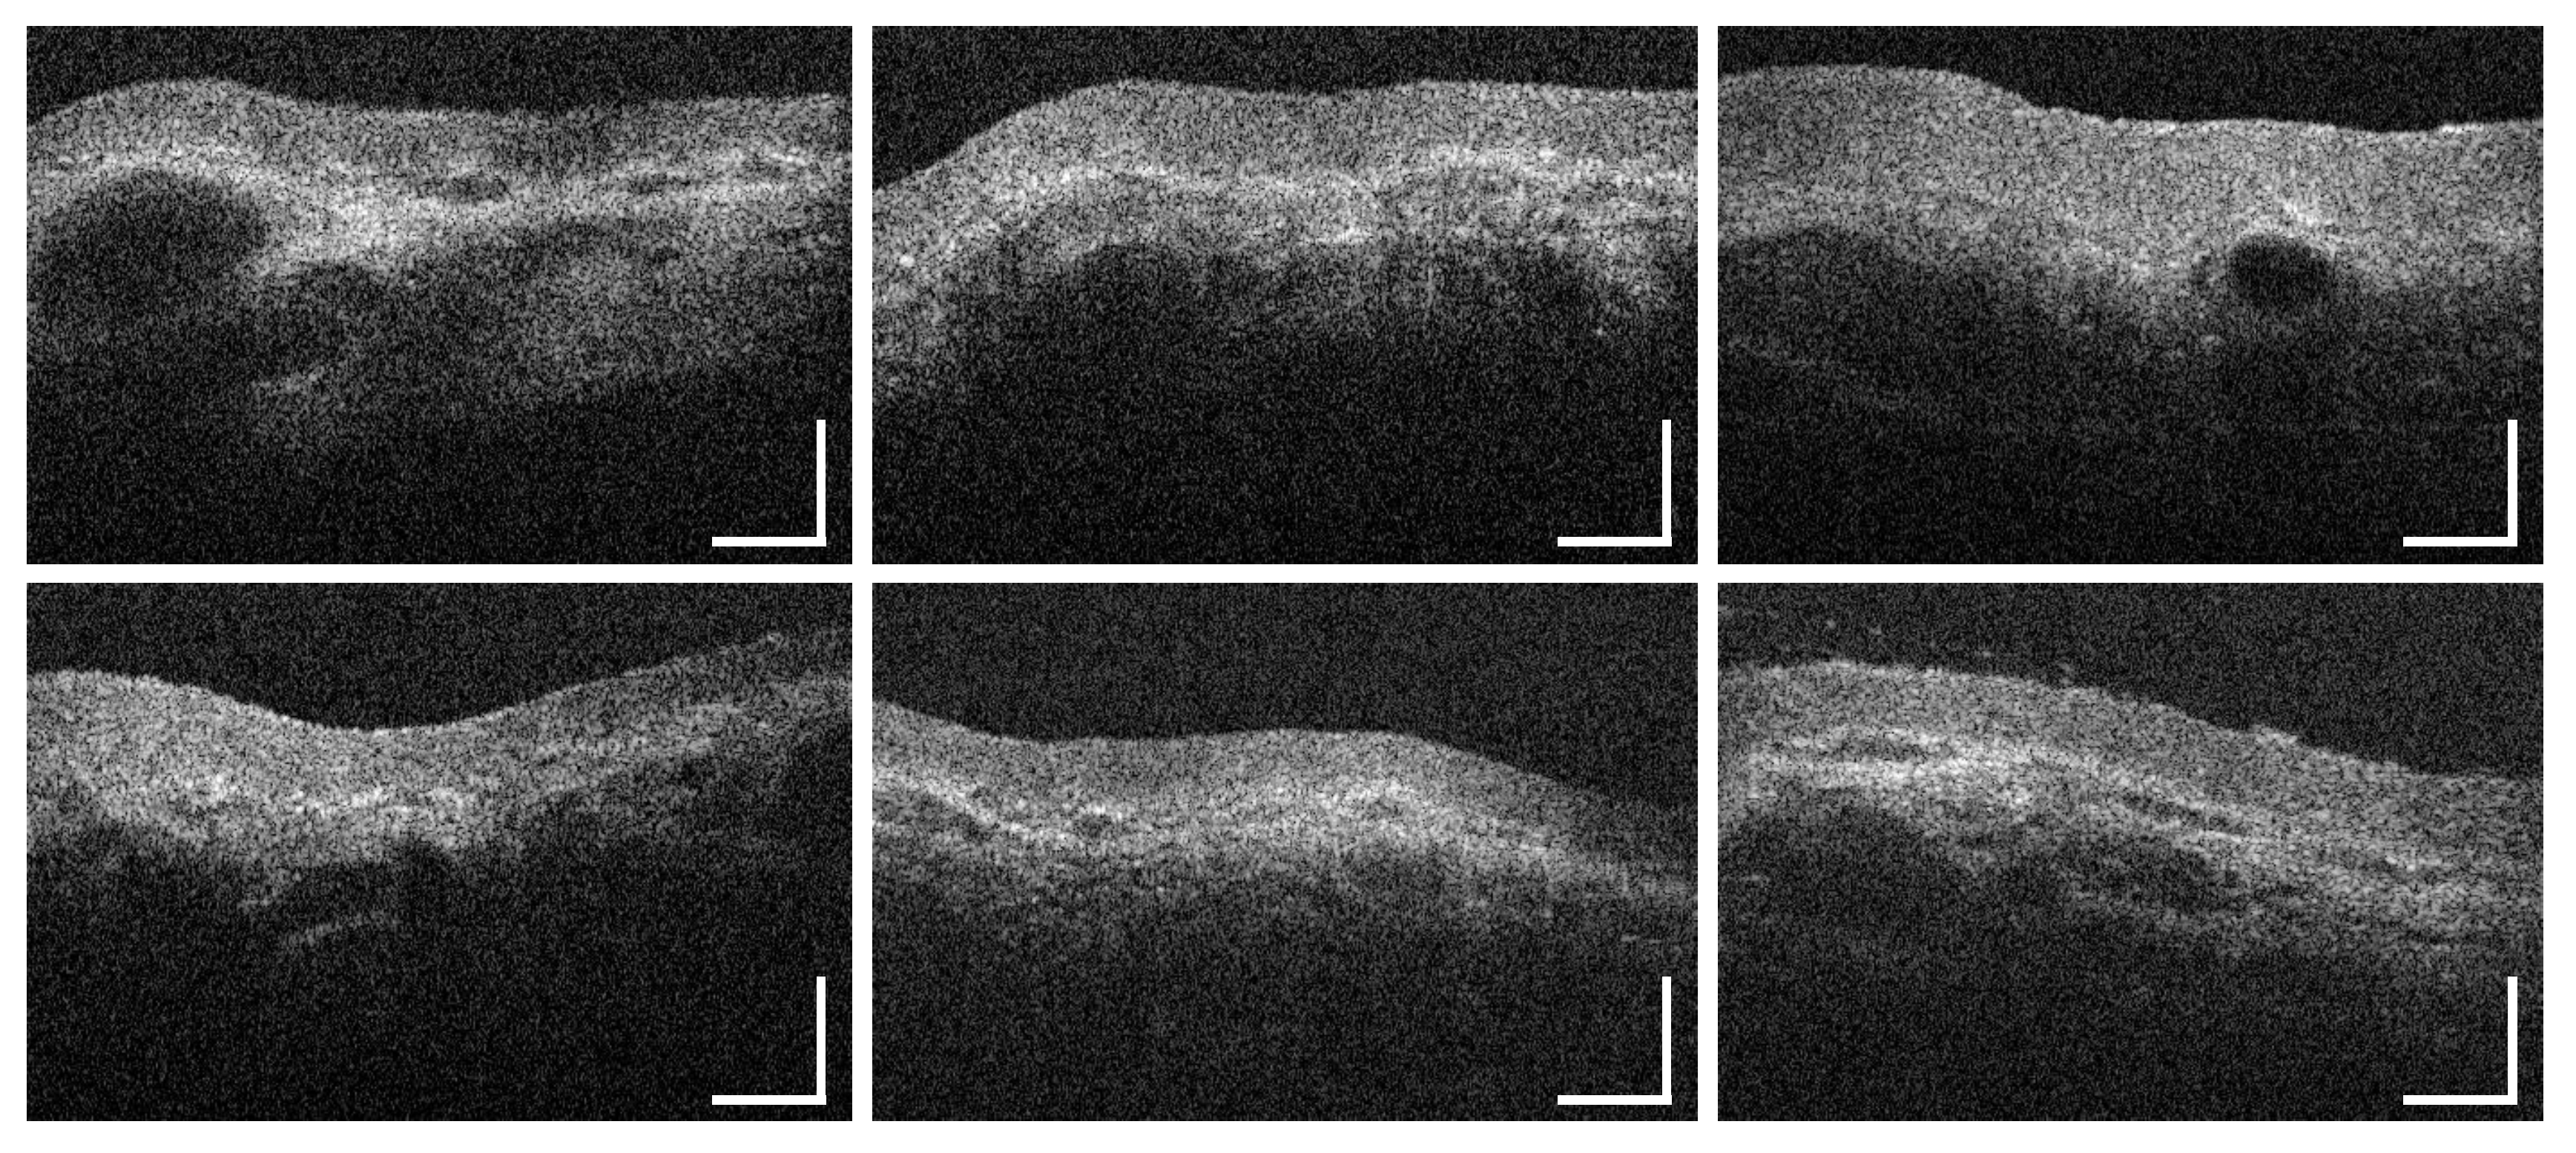

3.1. Labial and Alveolar Mucosa

3.2. Buccal Mucosa

3.3. Sublingual Mucosa

3.4. Hard Palate

3.5. Soft Palate and Oropharynx

3.6. Palatine Tonsils